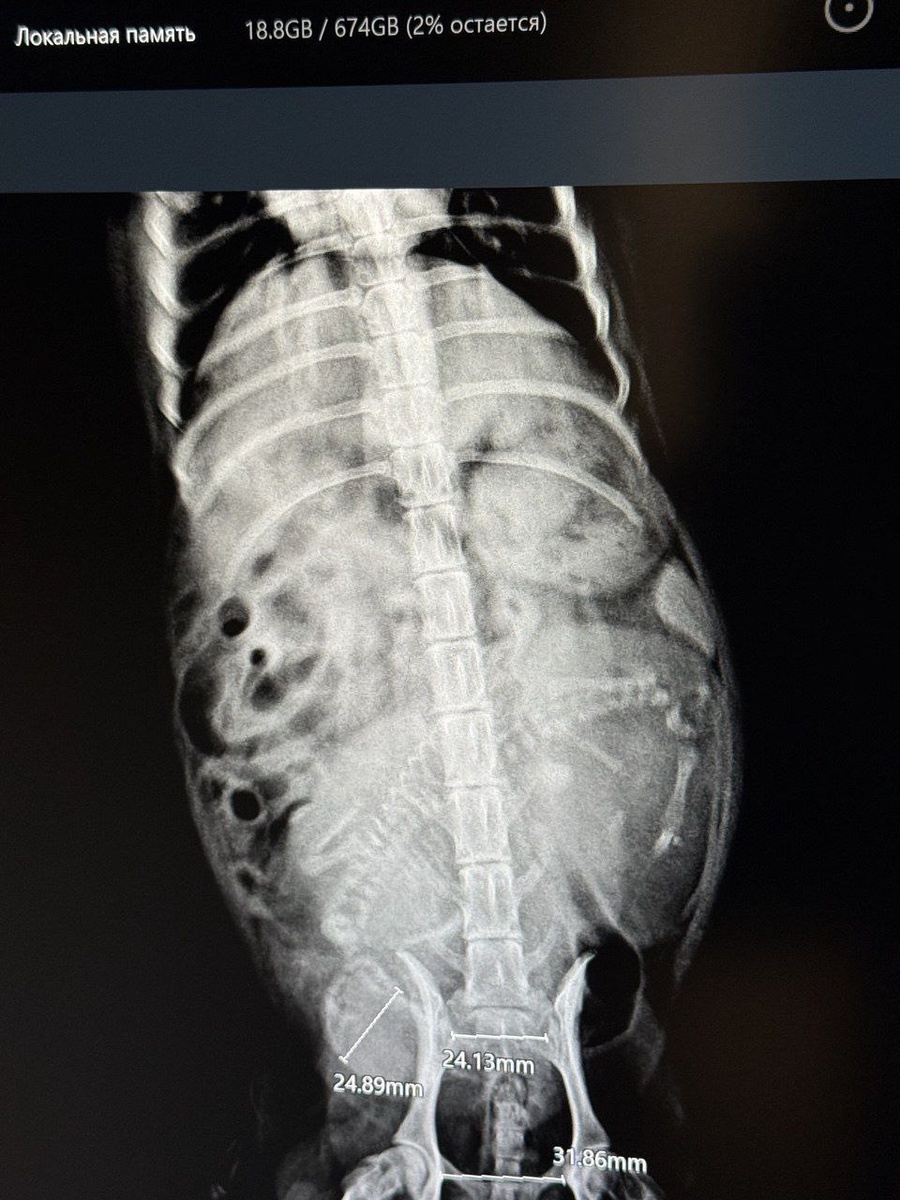

Хозяйка видит двоих. Надеется на троих